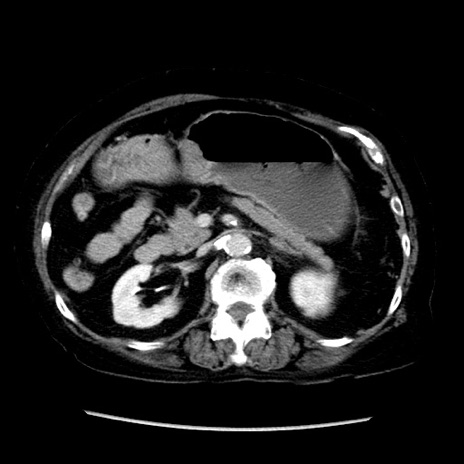

症例14(横断像)

【症例】 90歳代女性

【主訴】 腹痛・嘔吐

【現病歴】今朝から左側腹部痛を認めた。 経過観察していたが、嘔吐を認めたため来院。

【既往歴】 子宮癌術後

【身体所見】 意識清明、BP 127/54mmHg、P 98bpm Sp02 95%(RA)、BT 35.8°C、腹部平坦・軟腸ぜん動音聴取良好、右下腹部圧痛(+) 反跳痛なし

【データ】WBC 9800、CRP 0.46